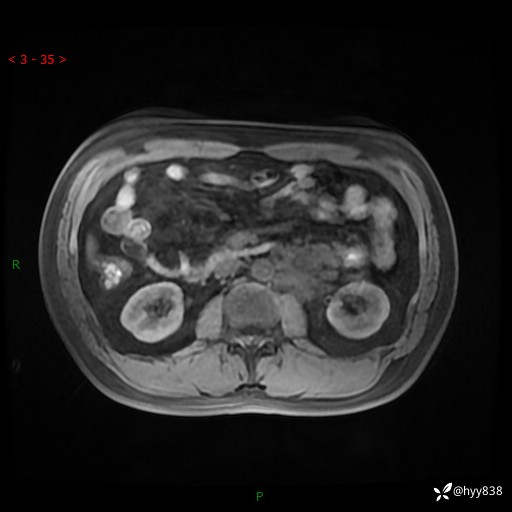

现病史:患者3月余前检查发现左侧腹膜后占位,大小约3.7*4.9cm,平素无腰疼,无肉眼血尿,无尿频尿急等不适,当时未特殊处理,在门诊复查CT提示左侧腹膜后占位,门诊拟“左侧腹膜后占位”收入院。 起病以来,患者精神佳,饮食、睡眠良好,大小便正常,体力体重无明显变化。

MRI增强